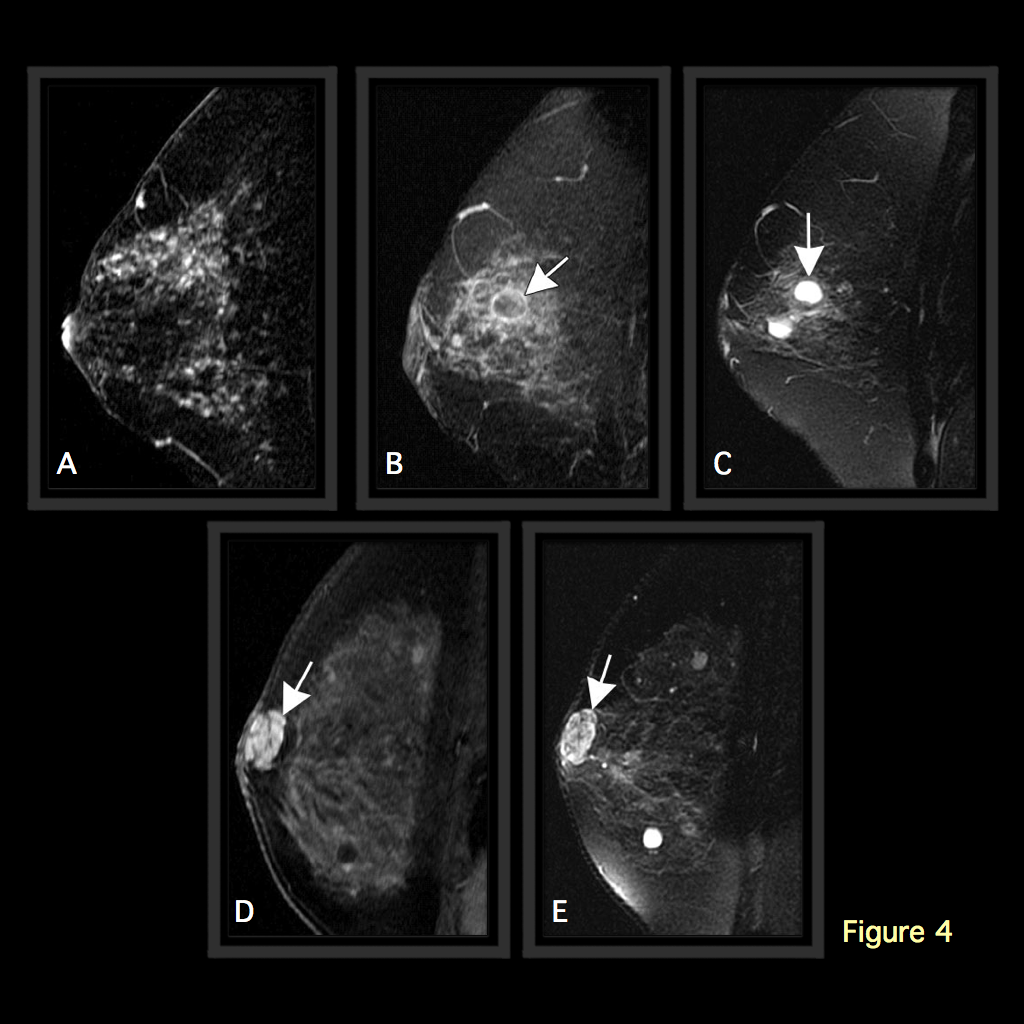

Μαγνητική μαστογραφία

Η μαγνητική μαστογραφία έχει προσφέρει τα τελευταία χρόνια τα μέγιστα στην διάγνωση και διερεύνηση ύποπτων αλλοιώσεων που έχουν αναδειχθεί στις άλλες απεικονιστικές μεθόδους.

Χρησιμοποιεί έναν συνδυασμό μαγνητικού πεδίου και ενδοφλέβιας χορήγησης σκιαγραφικού με σκοπό να αναδειχθούν περιοχές ή μάζες με διαταραγμένη πρόσληψη και ύποπτα χαρακτηριστικά.

Το μεγάλο πλεονέκτημα της μαγνητικής μαστογραφίας είναι η μεγάλη ευαισθησία της, δηλαδή η μεγάλη ικανότητα να αναγνωρίζει τον καρκίνο. Από την άλλη πλευρά, όμως, μειονέκτημά της είναι η χαμηλή της ειδικότητα. Τα πολλά ψευδώς θετικά αποτελέσματα (False alarms) της μεθόδου, δηλαδή η κινητοποίηση γιατρού και ασθενούς για μια βλάβη που μοιάζει με καρκίνο και τελικά αποδεικνύεται στη βιοψία ότι δεν είναι.